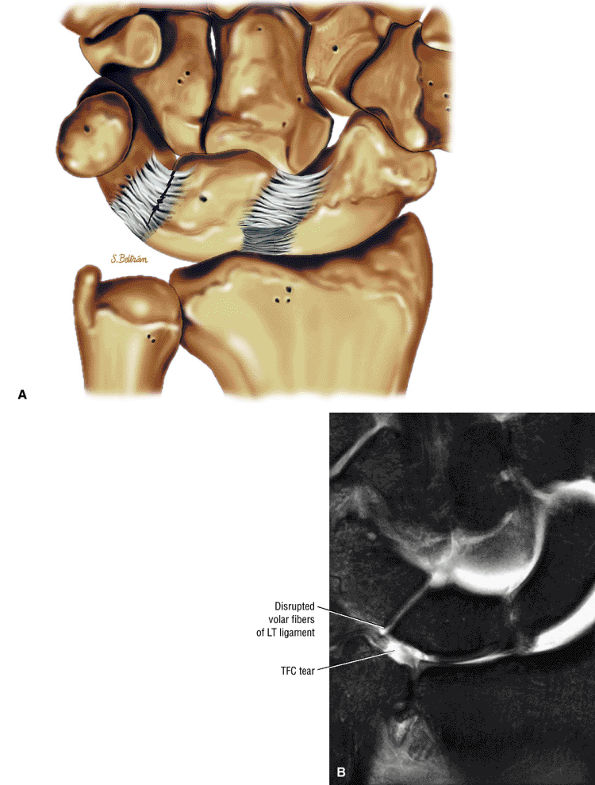

|

FIGURE 10.36 Triangular Fibrocartilage.